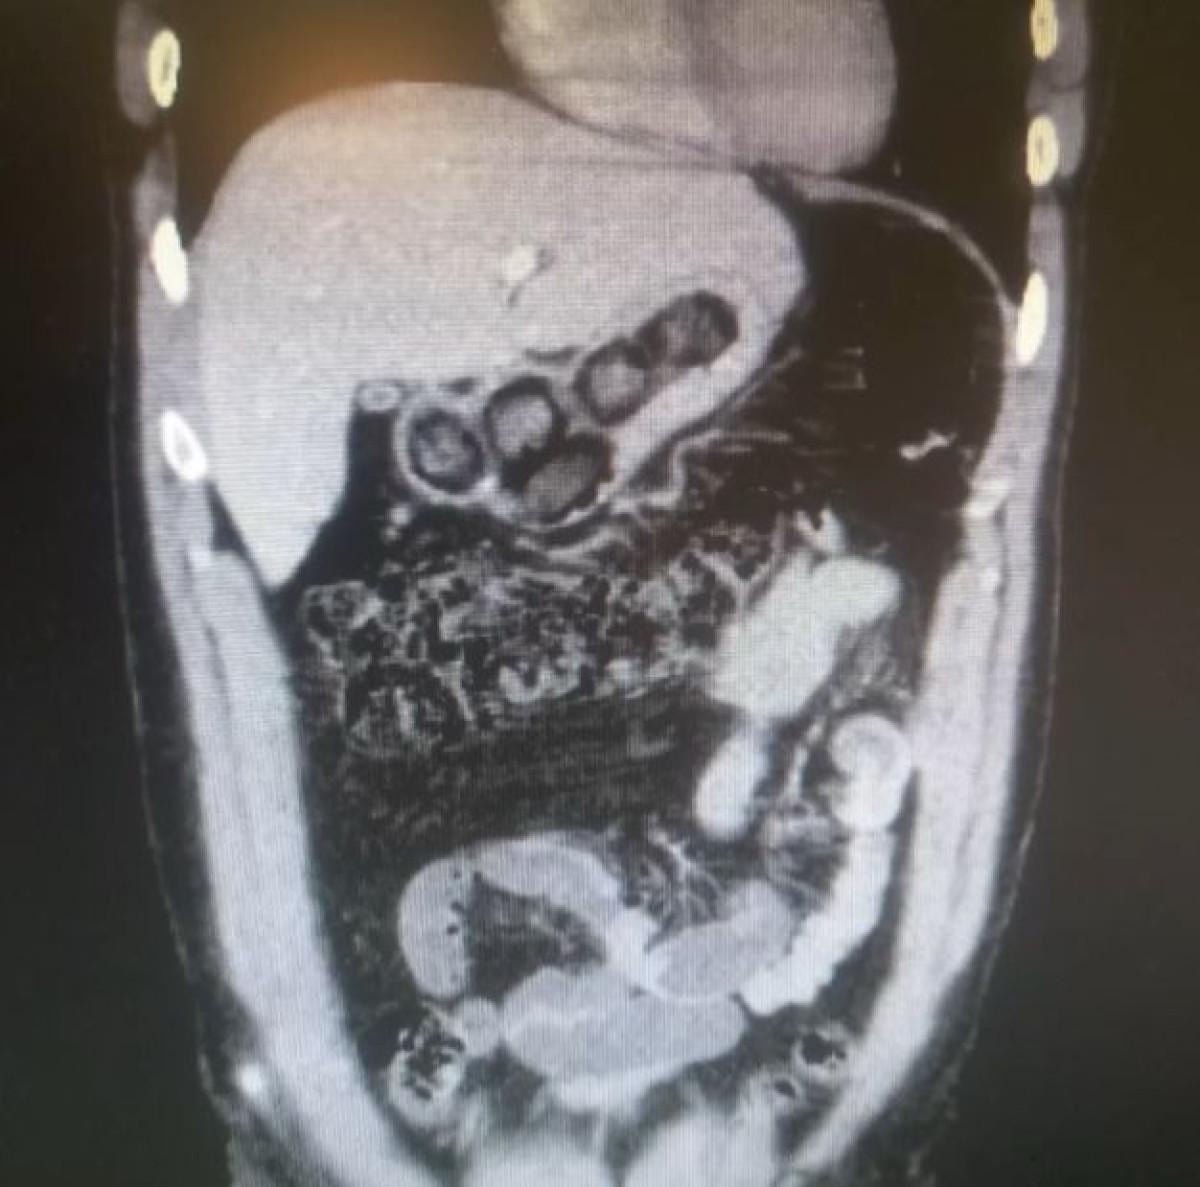

Röntgen ve ultrason sonrası kontrollerde, 3 şüphelinin midesinde uyuşturucu madde olduğu belirlendi.

17 KAPSÜL UYUŞTURUCU YUTTULAR

Şüphelilerin yaklaşık 17 kapsül halinde 212,8 gram uyuşturucu yuttuğu tespit edildi.

Kapsüller, sağlık ekibinin müdahalesiyle çıkarıldı.